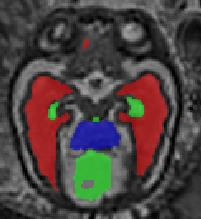

Limiting failures of machine learning systems is of paramount importance for safety-critical applications. In order to improve the robustness of machine learning systems, Distributionally Robust Optimization (DRO) has been proposed as a generalization of Empirical Risk Minimization (ERM). However, its use in deep learning has been severely restricted due to the relative inefficiency of the optimizers available for DRO in comparison to the wide-spread variants of Stochastic Gradient Descent (SGD) optimizers for ERM. We propose SGD with hardness weighted sampling, a principled and efficient optimization method for DRO in machine learning that is particularly suited in the context of deep learning. Similar to a hard example mining strategy in practice, the proposed algorithm is straightforward to implement and computationally as efficient as SGD-based optimizers used for deep learning, requiring minimal overhead computation. In contrast to typical ad hoc hard mining approaches, we prove the convergence of our DRO algorithm for over-parameterized deep learning networks with ReLU activation and a finite number of layers and parameters. Our experiments on fetal brain 3D MRI segmentation and brain tumor segmentation in MRI demonstrate the feasibility and the usefulness of our approach. Using our hardness weighted sampling for training a state-of-the-art deep learning pipeline leads to improved robustness to anatomical variabilities in automatic fetal brain 3D MRI segmentation using deep learning and to improved robustness to the image protocol variations in brain tumor segmentation. Our code is available at https://github.com/LucasFidon/HardnessWeightedSampler.